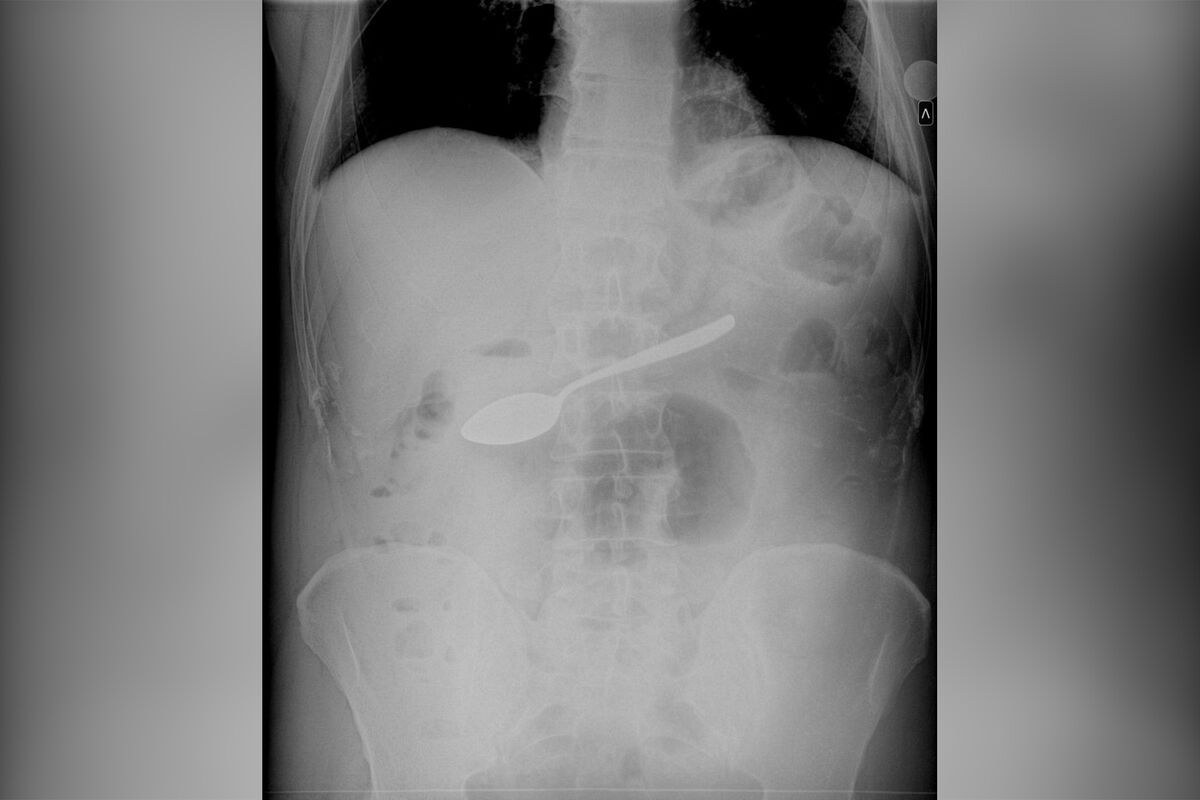

В Подмосковье из желудка мужчины извлекли десертную ложку. Об этом сообщает Telegram-канал «Разборчивым почерком».

По информации Telegram-канала, мужчина с инородным предметом в желудке попал в Мытищинскую больницу. Врачи в ходе осмотра установили, что этим предметом является десертная ложка — как она туда попала, не уточняется.

Медики приняли решение извлечь ложку обратным путем, а именно через пищевод с помощью специального зажима. Так им удалось избежать открытой операции.

Врачи успешно извлекли инородный предмет из желудка пациента, не травмировав его. Информации о том, как мужчина себя чувствует, не поступало.